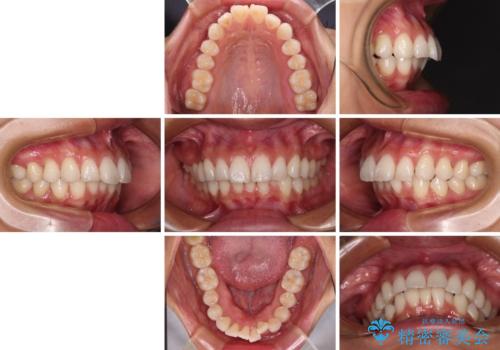

尖った前歯を引っ込めたい 目立たないワイヤー装置での抜歯矯正

- 飛び出した前歯を気にして来院された患者様です。

口元を引っ込めるために上下左右の第一小臼歯4本を抜歯することとしました。

結婚式を行う予定があるとのことで、表側のワイヤー装置で、速やかに治療を終えられるようにしました。

途中妊娠と出産がありましたが、予定よりも早く治療を終えることができました。